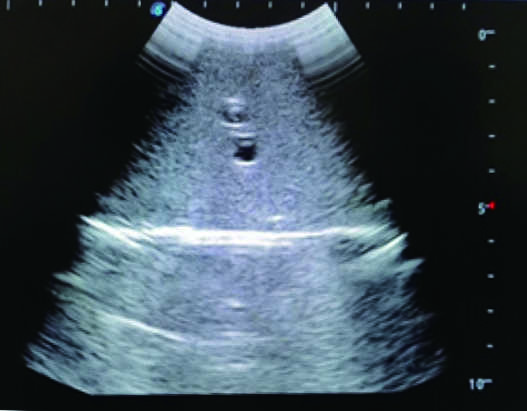

Femoral Arteriovenous Puncture & Abdominocentesis Ultrasound Training Model

This model is an ideal choice for ultrasound-guided femoral arteriovenous puncture & abdominocentesis training with true-to-life skin feel and touch, accurate anatomical structures and real clinical ultrasound images. Realistic resistance to needle tips and correct landmarks provide excellent hands-on experience.

2)  Real clinical ultrasound images with clear anatomical structures like intestines, part of the liver, arteries and veins, etc.